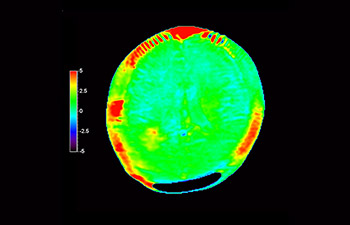

Numa sociedade para a qual os distúrbios neurológicos representam um fardo pesado, a Philips está empenhada em proporcionar uma extraordinária clareza de diagnóstico e orientações de tratamentos para todos os pacientes. Atualmente, embora a RM seja o padrão de excelência no diagnóstico por imagem em neuro-oncologia, sua precisão na classificação de tumores e na avaliação de acompanhamento dos tratamentos pode ser aprimorada. O APT (Amide Proton Transfer) 3D é um método exclusivo de diagnóstico por imagem por RM do cérebro sem contraste que aborda a necessidade de um diagnóstico mais confiante em neuro-oncologia. O APT 3D utiliza a presença de proteínas celulares endógenas para produzir um sinal de RM que se correlaciona diretamente com a proliferação celular, um marcador de atividade tumoral. O APT 3D pode auxiliar profissionais de saúde capacitados na diferenciação entre gliomas de baixo e de alto grau e a diferenciar a progressão tumoral do efeito do tratamento.1

com o APT 3D